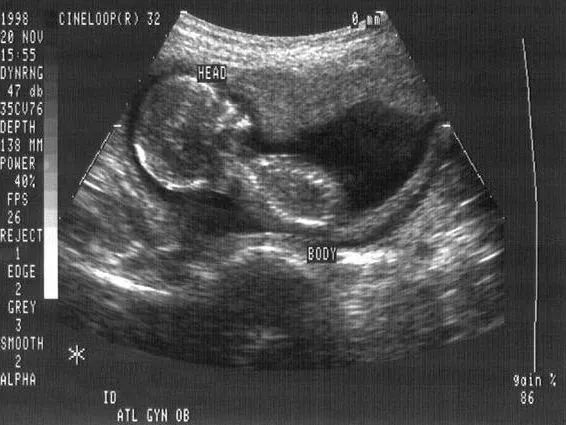

对于一些饱受生育之苦的女性而言,“机器人妈妈”或许可以她们面对生育绝境时所幻想的救世主。特别是对于许多深受不孕不育困扰的家庭而言,成功怀孕这件事情,并不完全是科学能解决的,“更多的时候是缘分和命运”。 “如果真有成熟的机器人子宫出现,我很欢迎”。正在借助试管婴儿技术备孕的文心告诉「有界UnKnown」,“至少不需要用我的身体来尝试,我用了这么多激素药物,说实话,真不知道以后身体会有什么后遗症。”近期文心刚结束第四次取卵,为了让卵子快速长大,她需要连续10天口服克罗米芬、来曲唑,在肚皮上注射促排药物果纳芬、在臀部注射尿促性素。“每次取卵前,我基本都要反复前往医院,每天打针、隔日抽血检测性激素、B超检测卵泡生长状况”。最大的“深渊”是守着看不见的黑洞,不知道什么时候才能熬出头。吃药打针取卵、吃药打针移植,这个过程像莫比乌斯环一样,反复循环。“在生殖科,如果你大声地告诉医生你怀孕了,那么,你遭受到的眼光里没有祝福,只有嫉妒”,文心说,在备孕的这五年里,她的内心都变得“黑暗”了。“这次历经艰辛,我也只取了5颗卵”,相比较于前三次,分别取卵2枚、0枚、3枚相比,这一次已经是收获最大的一回。取卵只是第一步,卵子和精子能否形成质量足够好的胚胎是第二大关,文心这四次一共获卵10枚,但最终配成胚胎的也只有四枚,“医生说可能是我们夫妻年纪偏大,精卵结合的质量不高。”除了四次取卵,文心马上要经历第四次移植手术,为了让子宫模拟一个成熟的受孕环境,每次移植之前文心都需要再度口服药物或打针半个月,并且每隔两三天要做B超和抽血检查。“每次躺在移植手术台的那一刻,我都觉得快要熬到头了”,但是每次到了“开奖日”,测孕纸上雪白的一片,都让文心自我怀疑、绝望。“我好像能做的都做了,我不知道重来一遍是不是会有结果”,四次取卵、三次移植,文心已经上了7次手术台,她想过放弃,但是一个她自己都认为荒谬的玄学信念让她想再试一次。“最近我总看到数字‘4’,比如我一抬头就看到时间停留在下午4:44,我一进商场就看到标价44元的日用品、444元的折后小家电”,“或许这是我的幸运数字”,“我已经取卵4次,如果顺利,马上要经历第4次移植,或许这次,会有奇迹发生。”文心挣扎在“怀不上”的悬崖,似乎无法前进,但也不想后退。而经历2次取卵、5次移植的秋丽,刚刚成功上岸,但她的状态也没有了刚怀孕的惊喜,“保胎不易,我的凝血偏高,每天都要注射价值300元一针的肝素,还要输防止宫缩的注射液,口服各类保胎药物”。秋丽粗算了一下,“我大概打过四五百多针,肚子上已经没地方扎了。”小红书上相同经历的小姐姐,也在上岸后发图,晒自己曾经吃过的药、打过的针,苦涩地恭喜自己成功“上岸”。从经济层面,文心也调侃,“我们花的钱,够买好几个机器人了。”秋丽也已经算不清自己到底花了多少钱,“我在一家私立医院,这2年已经花了20多万,保胎现在也用了七八万了”,“我也不愿意去列详细的账单,因为过程中不知道成败,每一份账单刺眼的同时,也刺痛了我的心。”除了身体的疼痛、精神和经济的压力,她们还要面临职业危机的到来。“公司领导一听说我要做试管,以为我很快就要成为孕妇了”, 毕竟,大部分人都没有结束过辅助生殖技术,很难知晓其中的艰辛。文心自从公布试管计划后,部门的核心业务都将她排除在外,“加薪升职,离我越来越远。”也有一些女性为了规避职业危机,选择秘密进行,但文心认为“这很不现实,因为一旦启动流程,几乎隔三差五请假,你很难解释”。这些在备孕过程中的女性,在失去了平衡的职业与生活中,等待缘分的出现。如果真的有替她们怀胎十月的“机器人妈妈”,她们就可以从被困住的备孕人生中解脱出来。不仅对备孕者,对恐育者而言,“机器人妈妈”也是一剂良药。在小红书上,有一波丁克女性热衷讨论的话题:生育就是最大的骗局。这些痛斥生育是骗局的女性中,可能也有一些是已经生育的人,她们的先验经历,成为丁克们查看育后生活的窗口。她们抱着有孩子后的生活很美好的信念,艰辛生育,但生育后又发现,万里长征才踏出一小步,更大的挑战不在于生,而在于养。身材走样、胸部下垂、满肚子妊娠纹、脱发、溢奶,对于很多女性而言,接受自己产后变样的体型,都需要很大的勇气。而接踵而至的家庭矛盾也增添了产后抑郁的概率。“有了孩子后,夫妻的二人世界真正结束了”,生完孩子半年的林墨感慨,“生了一个孩子,家里至少多两个人,一个是孩子,一个是带孩子的老人”。三代同堂的生活,成为初做父母者新的课题。如果机器人可以生孩子,就可以帮助女性省略孕育过程的生理不适,也规避分娩时的阵痛压力,当然,也就不存在对产后身材恢复的焦虑。但就像蝴蝶效应,世间万物都有联系,牵一发而动全身,如果机器人妈妈将女性从生育之痛解脱,随之而来,也会面临更多挑战,比如婚姻和亲子关系的重构。